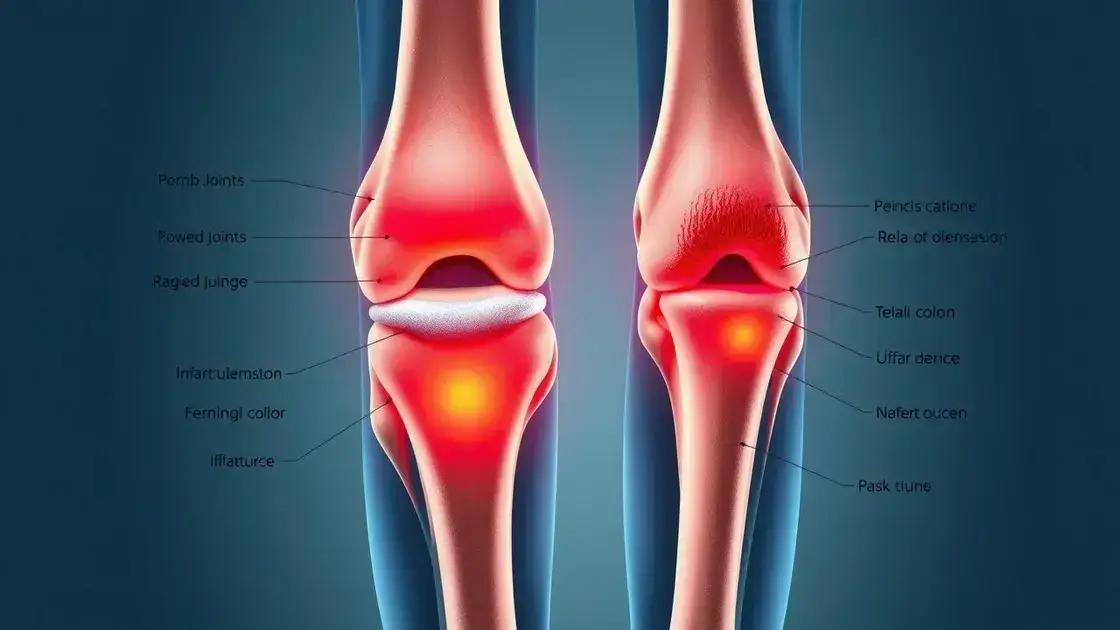

Entender o que provoca as dores nas juntas na terceira idade é fundamental para um tratamento adequado. O processo natural de envelhecimento traz mudanças significativas nas articulações, como o desgaste da cartilagem e a diminuição do líquido sinovial.

A artrite e artrose são as principais causadoras desse desconforto. A primeira é uma inflamação que causa inchaço e rigidez, enquanto a segunda resulta do desgaste natural das articulações com o tempo. Além disso, o sedentarismo e o excesso de peso podem agravar essas condições.

Sintomas Comuns das Dores nas Juntas

Os sintomas das dores nas juntas podem variar em intensidade e frequência, mas existem sinais característicos que merecem atenção especial. O reconhecimento precoce desses sintomas pode fazer toda diferença no tratamento.

Entre os sinais mais comuns, destacam-se:

- Rigidez matinal que dura mais de 30 minutos

- Inchaço visível nas articulações

- Dificuldade para realizar movimentos simples

- Sensação de calor na região afetada

- Crepitação (estalos) ao movimentar as juntas